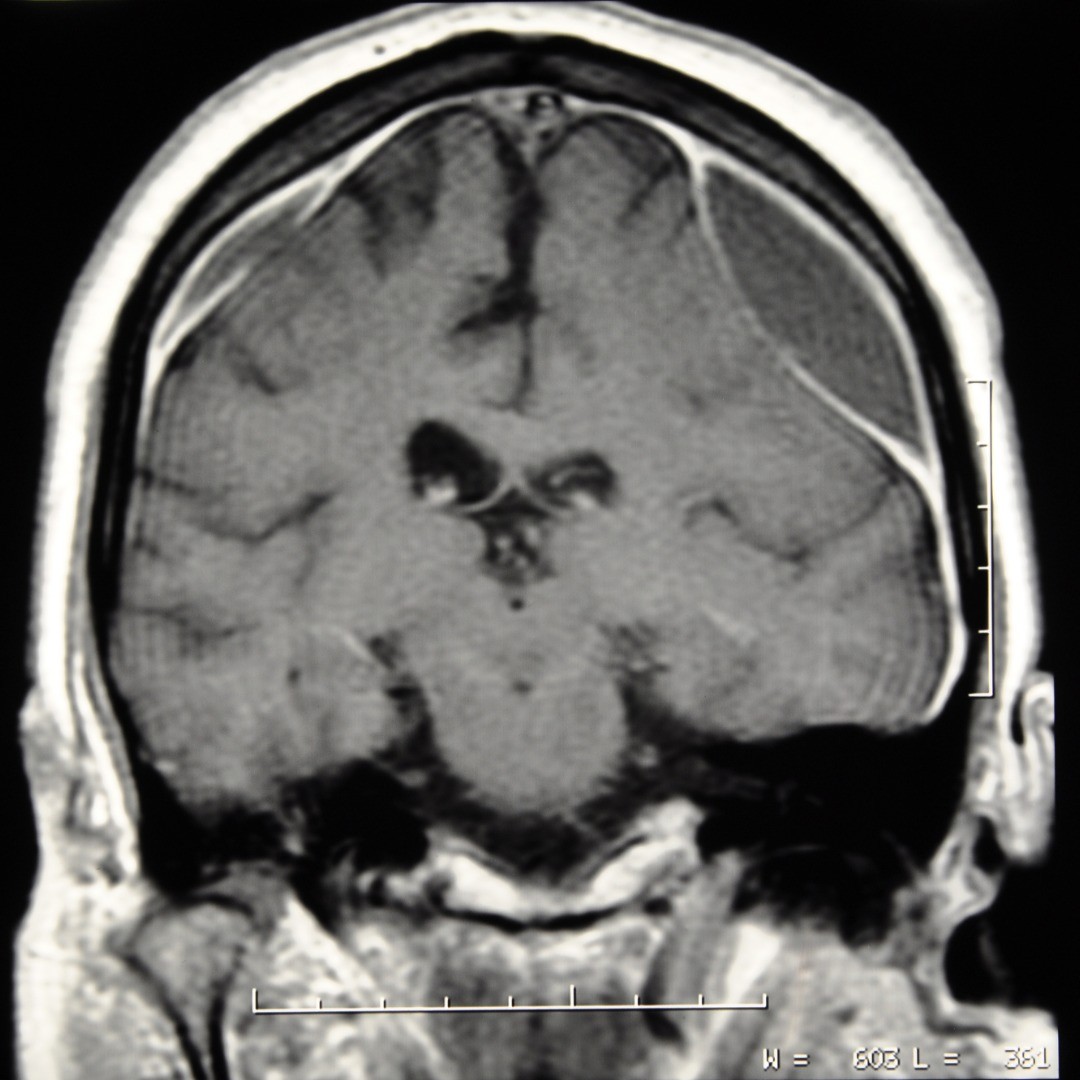

A craniotomy for subdural hematoma allows a neurosurgeon access through the skull via a small opening for the extraction of a blood clot on the exterior of the brain. These blood clots (hematomas) are underneath (sub) the dura mater (dural) or outer covering of the brain and occur when the blood vessels that traverse the space are ruptured.

The symptoms for a subdural hematoma resulting from a head injury can be immediate, known as an acute subdural hematoma, or can develop over time after an injury—sometimes even several weeks, called a chronic subdural hematoma. Symptoms can include:

A cerebral hematoma requires emergency medical attention to prevent neurological damage or death. At NSPC (NSPC Brain & Spine Surgery (NSPC)), we have neurosurgeons on call to take doctor referrals for emergency brain surgery in the New York area.